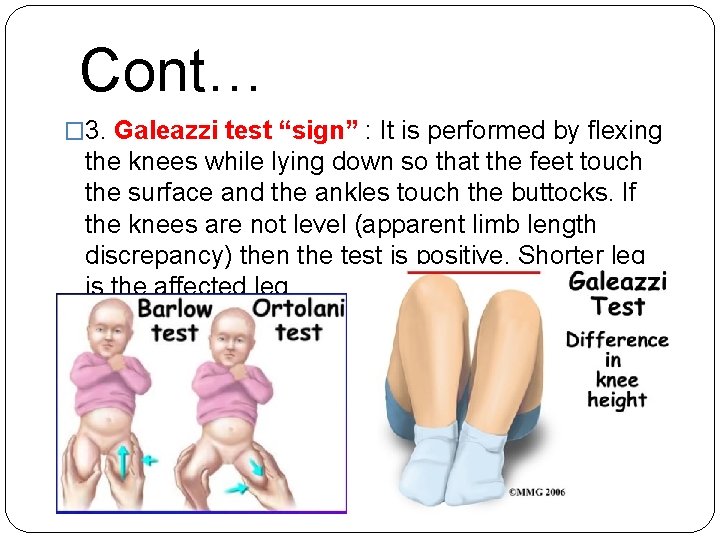

Cont… � 3. Galeazzi test “sign” : It is performed by flexing the knees while lying down so that the feet touch the surface and the ankles touch the buttocks. If the knees are not level (apparent limb length discrepancy) then the test is positive. Shorter leg is the affected leg.